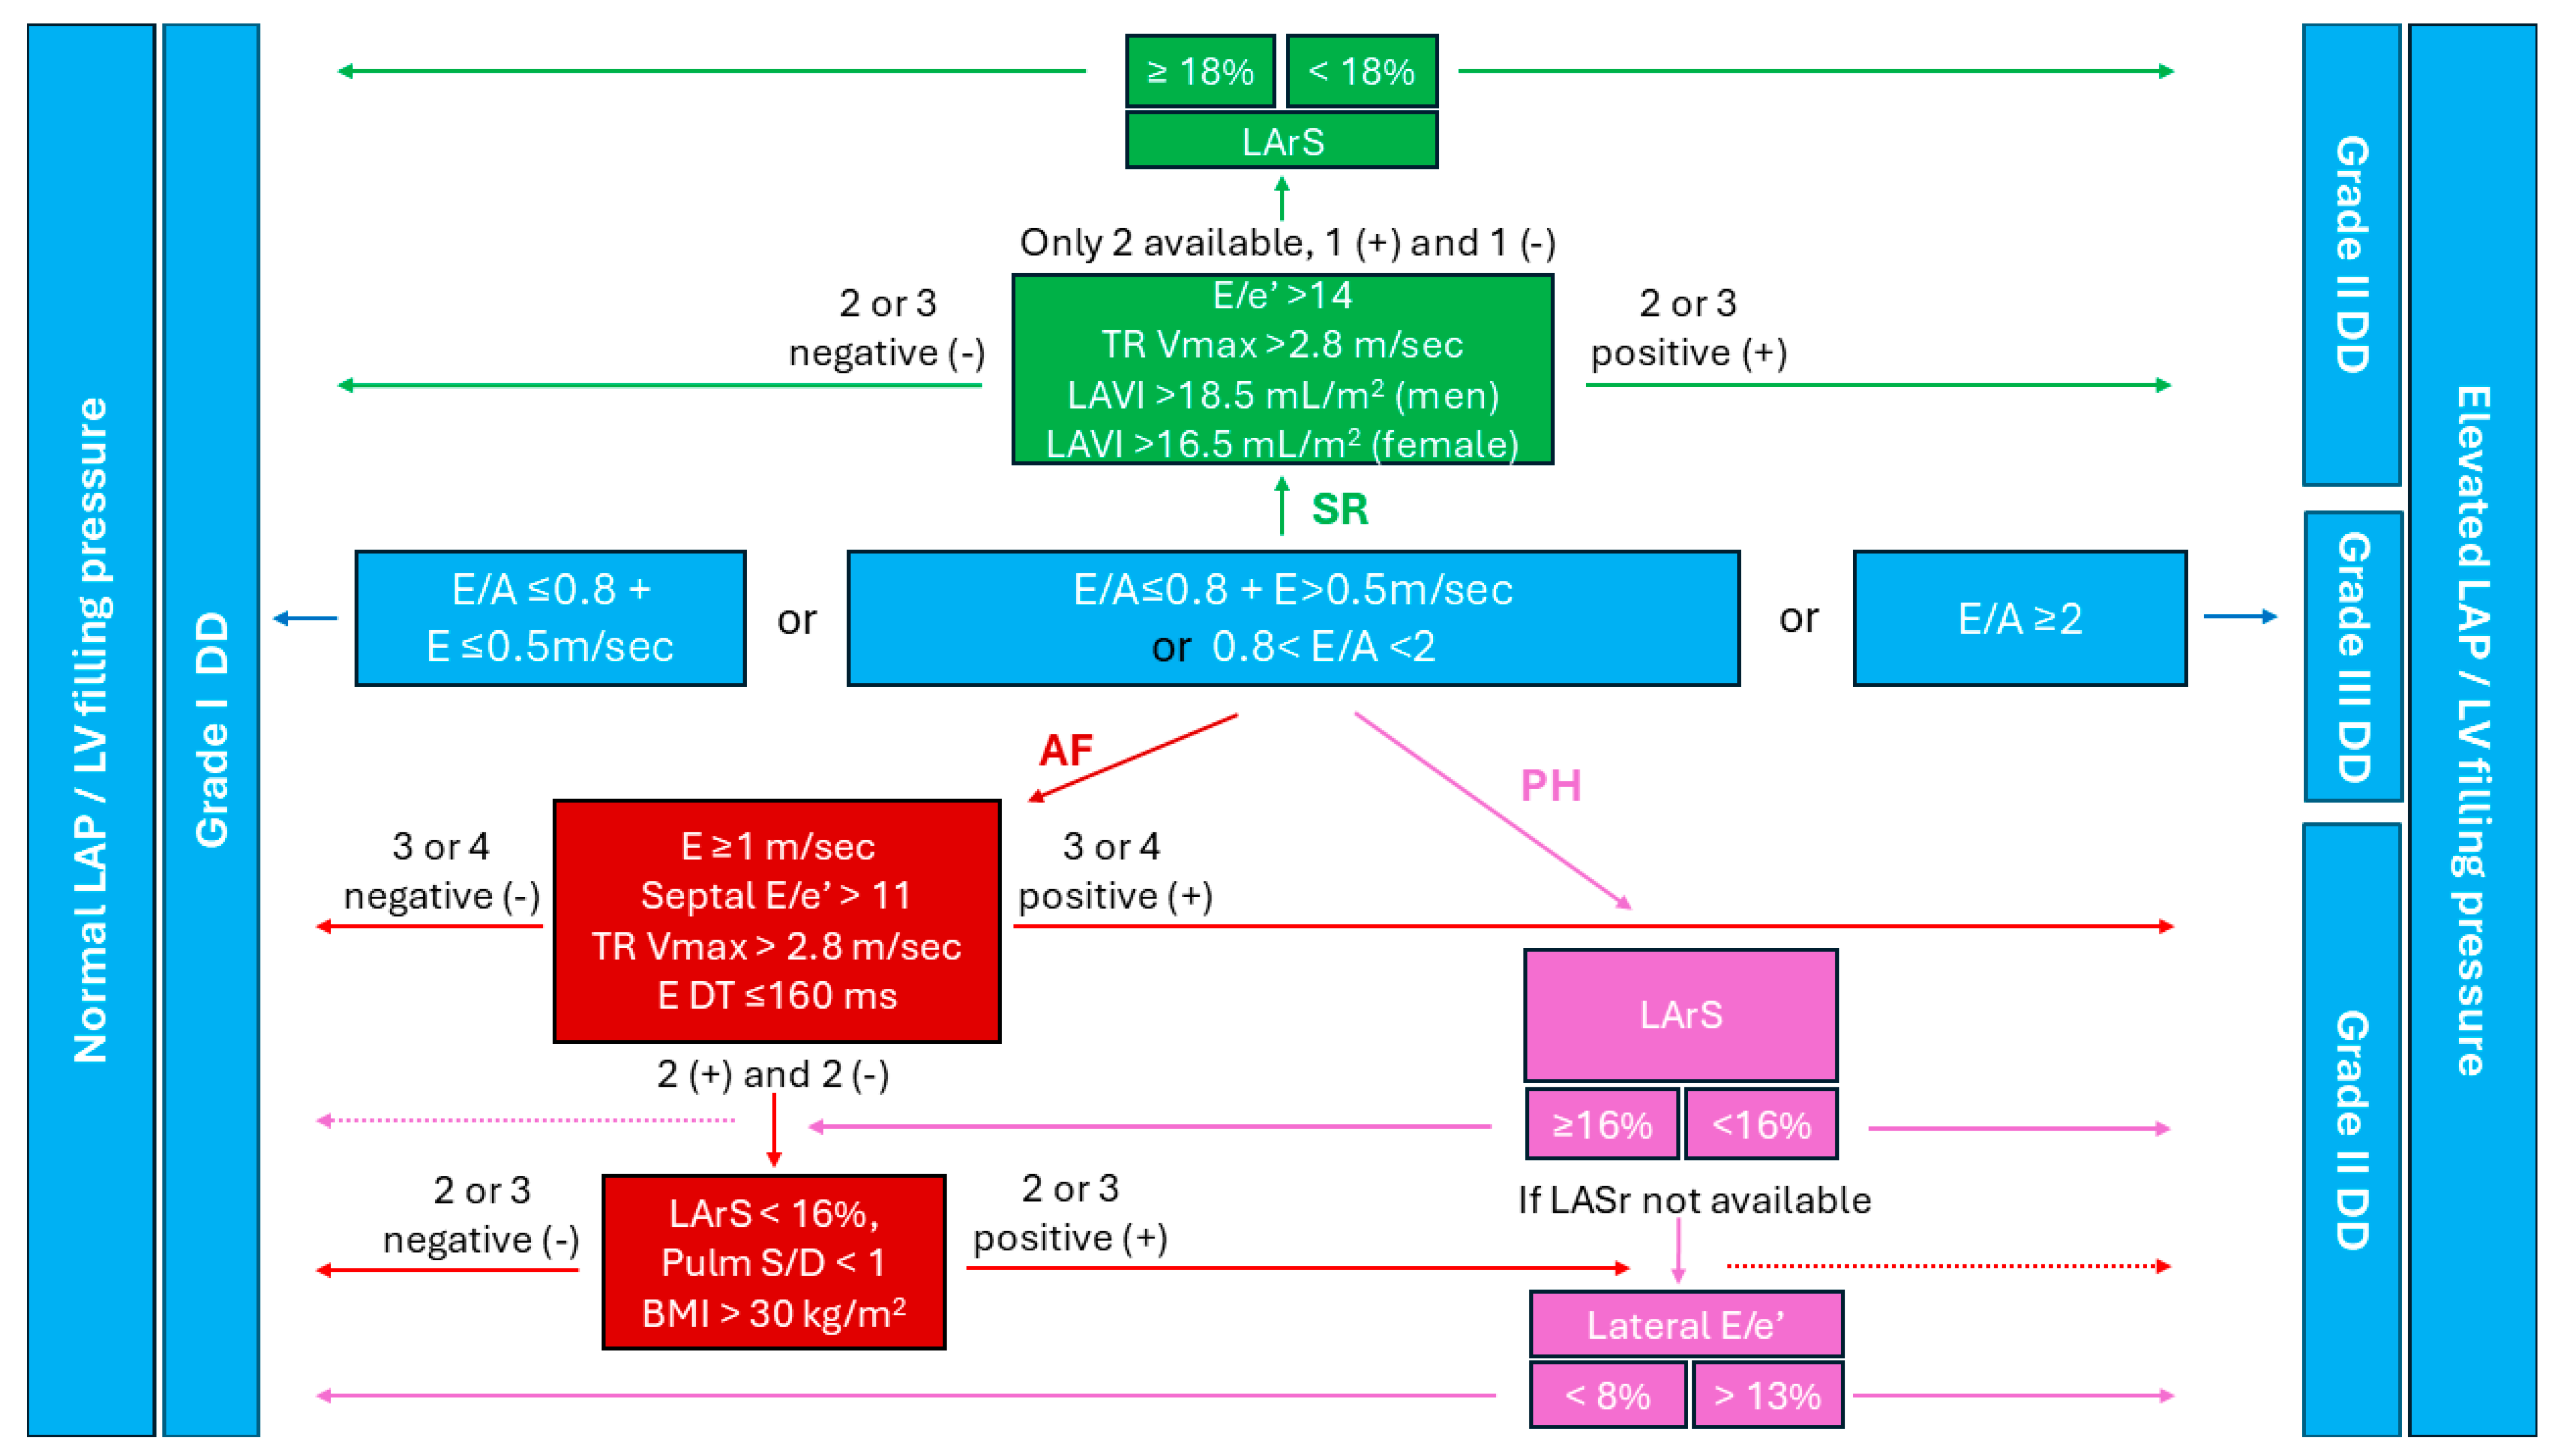

4. Diastolic Dysfunction Assessment in Individuals Who Are Obese in Sinus Rhythm

5. Diastolic Dysfunction Assessment in Individuals Who Are Obese in Atrial Fibrillation

6. Pulmonary Hypertension and Diastolic Dysfunction in Obese